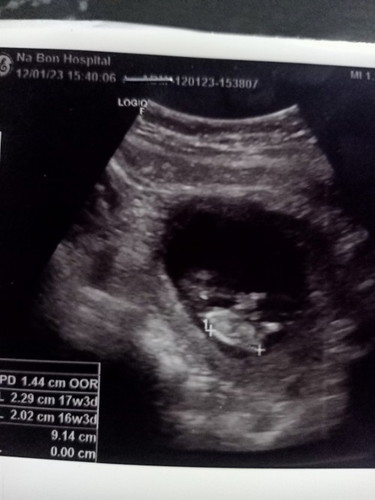

แม่ๆช่วยดูเพศหน่อยค่ะ

แม่ๆ คิดว่าน้องจะเป็นเพศไหนคะ แม่ไม่ค่อยแต่งตัวโซมมาก กินข้าวไม่ได้เลยคะแต่ กินของหวาน ได้ คลื่นไส้บ่อยด้วยคะ #ขอคำแนะนำหน่อยค่ะ #ท้องแรกคะ